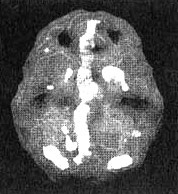

Мозг Стивена. Суицидальные мысли

Иллюстрация к книге — Измените свой мозг - изменится и жизнь! [i_082.jpg]

Иллюстрация к книге — Измените свой мозг - изменится и жизнь! [i_083.jpg]

Обратите внимание на выраженно повышенную активность в левой височной доле и в поясной системе (стрелки).